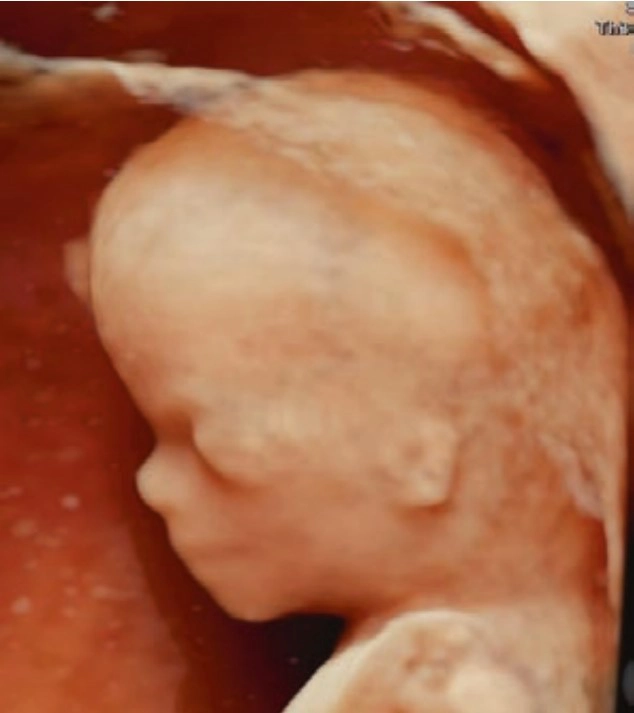

Phôi thai và Giải phẫu siêu âm mặt cổ thai nhi (Embryology and Anatomy of the Face and Neck)

• Giải phẫu

• Phôi thai và Giải phẫu siêu âm mặt cổ thai nhi (Embryology and Anatomy of the Face and Neck)